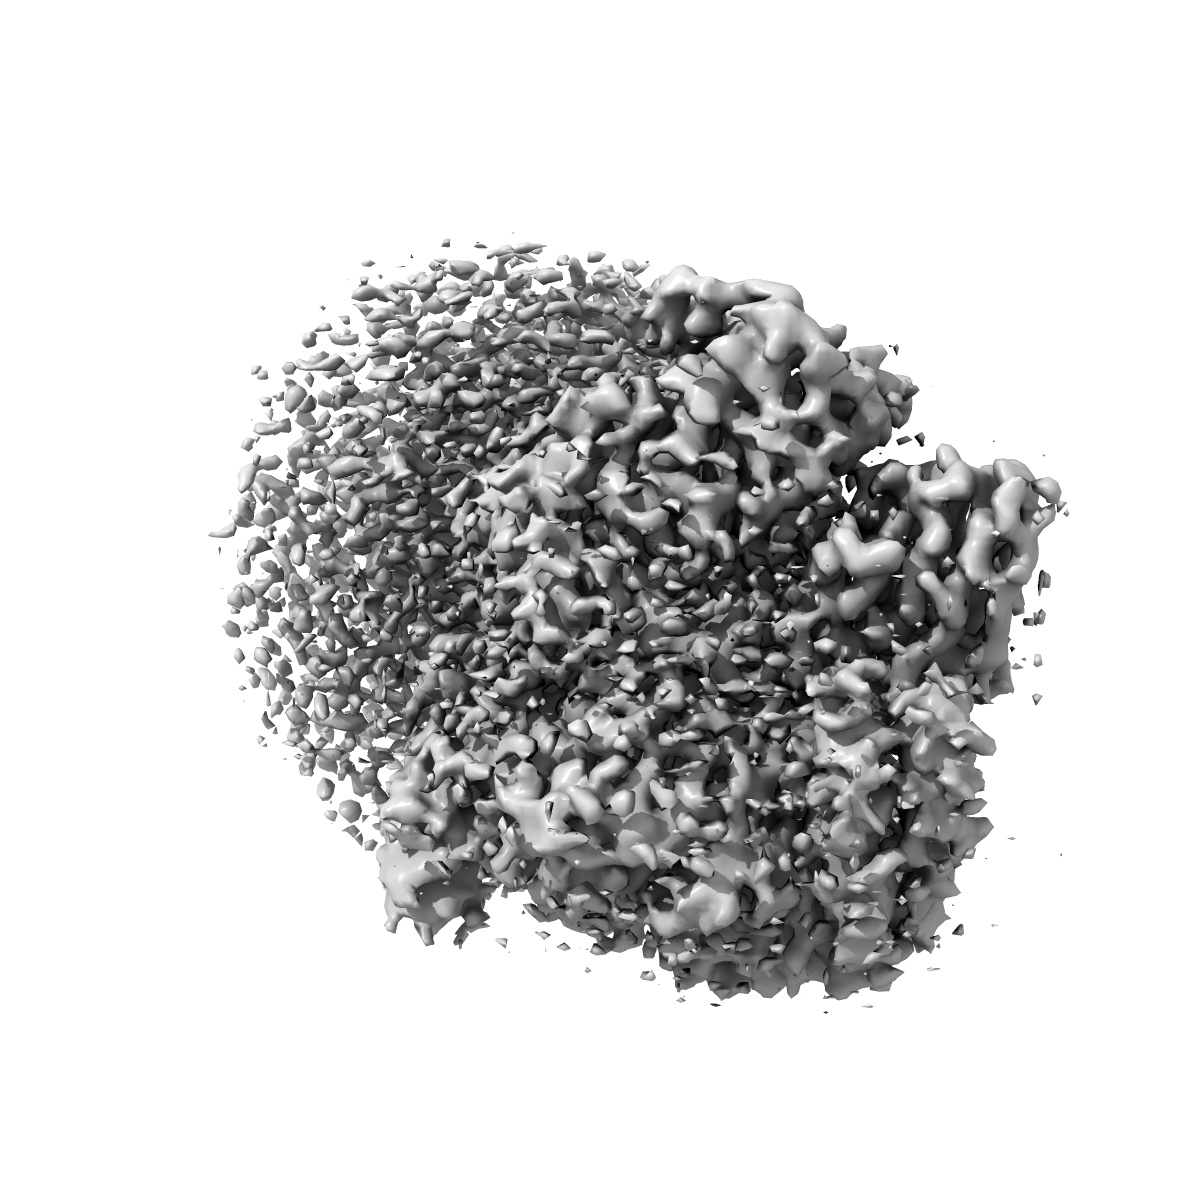

Cryo-EM structure of apomorphine-bound dopamine receptor 1 in complex with Gs protein

Single-particle3.0 Å